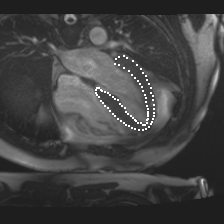

Accurate segmentation and motion estimation of myocardium have always been important in clinic field, which essentially contribute to the downstream diagnosis. However, existing methods cannot always guarantee the shape integrity for myocardium segmentation. In addition, motion estimation requires point correspondence on the myocardium region across different frames. In this paper, we propose a novel end-to-end deep statistic shape model to focus on myocardium segmentation with both shape integrity and boundary correspondence preserving. Specifically, myocardium shapes are represented by a fixed number of points, whose variations are extracted by Principal Component Analysis (PCA). Deep neural network is used to predict the transformation parameters (both affine and deformation), which are then used to warp the mean point cloud to the image domain. Furthermore, a differentiable rendering layer is introduced to incorporate mask supervision into the framework to learn more accurate point clouds. In this way, the proposed method is able to consistently produce anatomically reasonable segmentation mask without post processing. Additionally, the predicted point cloud guarantees boundary correspondence for sequential images, which contributes to the downstream tasks, such as the motion estimation of myocardium. We conduct several experiments to demonstrate the effectiveness of the proposed method on several benchmark datasets.